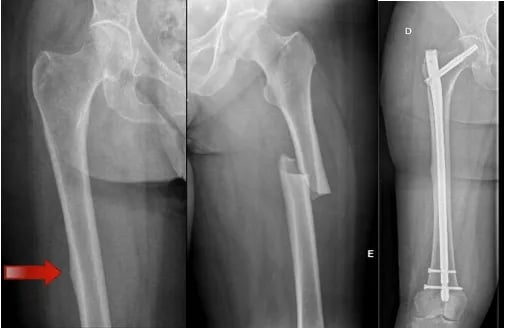

Fratura atípica de fêmur

A fratura atípica de fêmur é uma condição infrequente, que ocorre em pacientes que fazem uso prolongado de bifosfonatos, como o alendronato ou risedronato.

Utiliza-se essas medicações para o tratamento da osteoporose. Elas atuam impedindo que as células do organismo retirem cálcio do osso. Inicialmente, esse processo é interessante para evitar a progressão da osteoporose.

Entretanto, após longos períodos de uso (geralmente mais de 10 anos), essa medicação pode interromper o processo de renovação do osso (que ocorre pelo equilíbrio de retirada e deposição de cálcio), fazendo com que o osso fique duro, porém frágil, assim como um galho verde congelado.

Antes de a fratura propriamente dita ocorrer, o paciente apresenta uma dor na coxa por algumas semanas, causada por uma microfratura no osso, algumas vezes referida como dor no fêmur.

Portanto, pacientes idosos e/ou que fazem uso dessas medicações há muito tempo, e que apresentam dor na coxa ou no quadril, devem ser investigados para essa condição, com RX e Ressonância Magnética.

Como trata-se a fratura típica de fêmur?

Caso os exames apontem a presença de uma microfratura ou espessamento na cortical lateral do fêmur, é mandatório que seja feita uma cirurgia preventiva, com a colocação de uma haste metálica dentro do fêmur, para evitar a ocorrência de uma fratura completa, uma vez que essas fraturas têm um processo de consolidação mais difícil do que fraturas convencionais, justificando a realização da cirurgia profilática.

Caso ocorra a fratura completa, o paciente apresenta muita dor na coxa e não consegue se levantar. Desse modo, esses pacientes geralmente são levados de ambulância para o hospital, necessitando de internação e cirurgia em caráter de urgência.